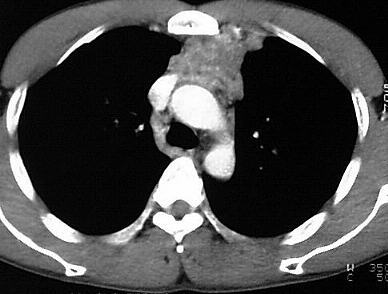

Tumoren

Insbesondere bei Rauchern hat das Bronchialkarzinom eine hohe Inzidenz. Histologisch lassen sich in abnehmender Häufigkeit Plattenepithelkarzinome, kleinzellige Karzinome, Adenokarzinome und grosszellige Karzinome unterscheiden.

Klinisch kann zwischen dem zentralen und dem peripheren Bronchialkarzinom unterschieden werden. Das zentrale Bronchialkarzinom ist im zentralen Bronchialbaum gelegen und zeigt sich in der CT als weichteildichte Raumforderung mit Verlagerung und Stenosierung der Luftwege. Daraus können Minderbelüftungen und nachgeschaltete Infiltrationen resultieren. Als Zeichen einer pleuralen Infiltration sind häufig blutige Pleuraergüsse vorhanden. Im fortgeschrittenen Tumorstadium ist ein Tumoreinbruch in das Mediastinum möglich.

Ein peripheres Bronchialkarzinom ist innerhalb des Lungengewebes gelegen. Computertomographisch imponiert es als weichteildichte intrapulmonale Raumforderung. Charakteristisch ist das Auftreten der Corona radiata, feiner strahlenförmiger Tumorausläufer in die Lungenperipherie sowie von strangförmigen Pleurafingern, die zur Pleura visceralis verlaufen. Bei Plattenepithelkarzinomen kann es zu Einschmelzungen kommen.

Mediastinale und hiläre Lymphknotenmetastasen sind im fortgeschrittenen Tumorstadium häufig.

Lymphome

Mediastinale Lymphknotenvergrösserungen kommen bei Hodgkin-Lymphomen in mehr als 50% und bei Non-Hodgkin-Lymphomen in ca. 20% der Fälle vor. Die Lymphome sind computertomographisch als noduläre oder unstrukturierte weichteildichte Raumforderungen gekennzeichnet, die paratracheal, paravertebral, retrokrural, perikaval, präaortal und retrosternal gelegen sind.